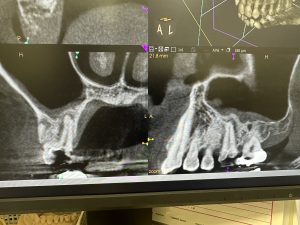

次は、歯性上顎洞炎の根管治療2カ月後

だいぶ回復💪